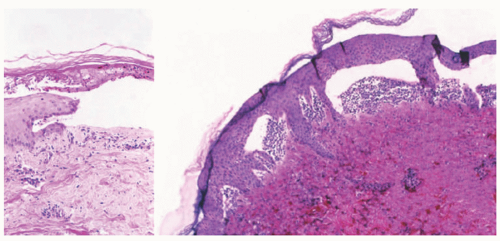

![]() FIGURE 4-22. Epidermolysis bullosa acquisita. The left image shows a relatively infiltrate-poor subepidermal bulla; a few neutrophils can be seen within degenerated portions of the epidermis and in the papillary dermis. The right image shows papillary neutrophilic microabscesses—a feature in some examples of epidermolysis bullosa acquisita that can also be seen in other immunobullous diseases.